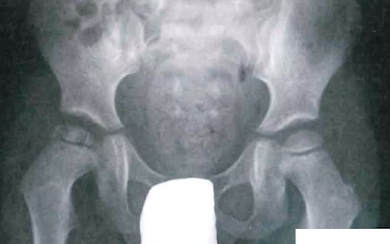

Fractura subcapital desplazada en paciente menor de 65 años

A

Reducción cerrada y osteosíntesis con tornillos canulados

Si 65-75: prótesis total

>75 a: prótesis parcial